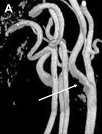

МРТ – это компьютерное исследование, тоже скрининговый метод, он дороже УЗДГ почти в 4 раза. Показанием для проведения этого метода исследования служат подозрения на патологические изменения в структурах мозга, в том числе и в сосудистом русле, находящемся внутри черепной коробки (рис. 3).

Рис. 3. МРТ-реконструкция брахиоцефальных артерий.

(Магнитно-резонансная ангиография артерий). Белыми стрелками показаны: сужение (стеноз) правой внутренней сонной артерии (А); стеноз левой сонной артерии и закупорка (окклюзия) правой (В); окклюзия левой внутренней сонной артерии (В); стеноз правой позвоночной артерии (Г); извитость правой и левой сонных артерий (Д)).

Рис. 3. МРТ-реконструкция брахиоцефальных артерий.(Магнитно-резонансная ангиография артерий). Белыми стрелками показаны: сужение (стеноз) правой внутренней сонной артерии (А); стеноз левой сонной артерии и закупорка (окклюзия) правой (В); окклюзия левой внутренней сонной артерии (В); стеноз правой позвоночной артерии (Г); извитость правой и левой сонных артерий (Д)).